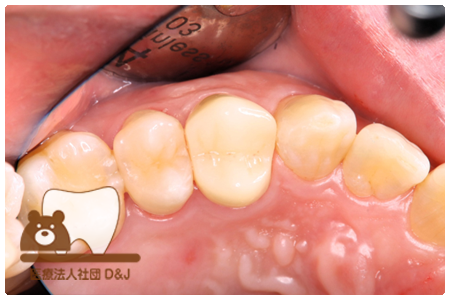

症例3フリジルコニアクラウン 左上6

治療前

治療後

59歳 男性

- 治療内容

- 虫歯で大きく失われた歯に対して、土台としてファイバーコアを使用し、その上にフルジルコニア製の被せ物を装着しました。見た目と強度を両立した自由診療の治療です。

- 治療期間

- 根の治療含めて3カ月半

- 費用

- 自費

フリジルコニアクラウン:77,000円(税込)

(R8.2月時点)

- その他の治療の費用は含まれておりません。

- リスク・副作用

- 強い力が加わると割れる可能性があります。また、噛み合わせや歯ぎしりの影響で脱離することがあります。